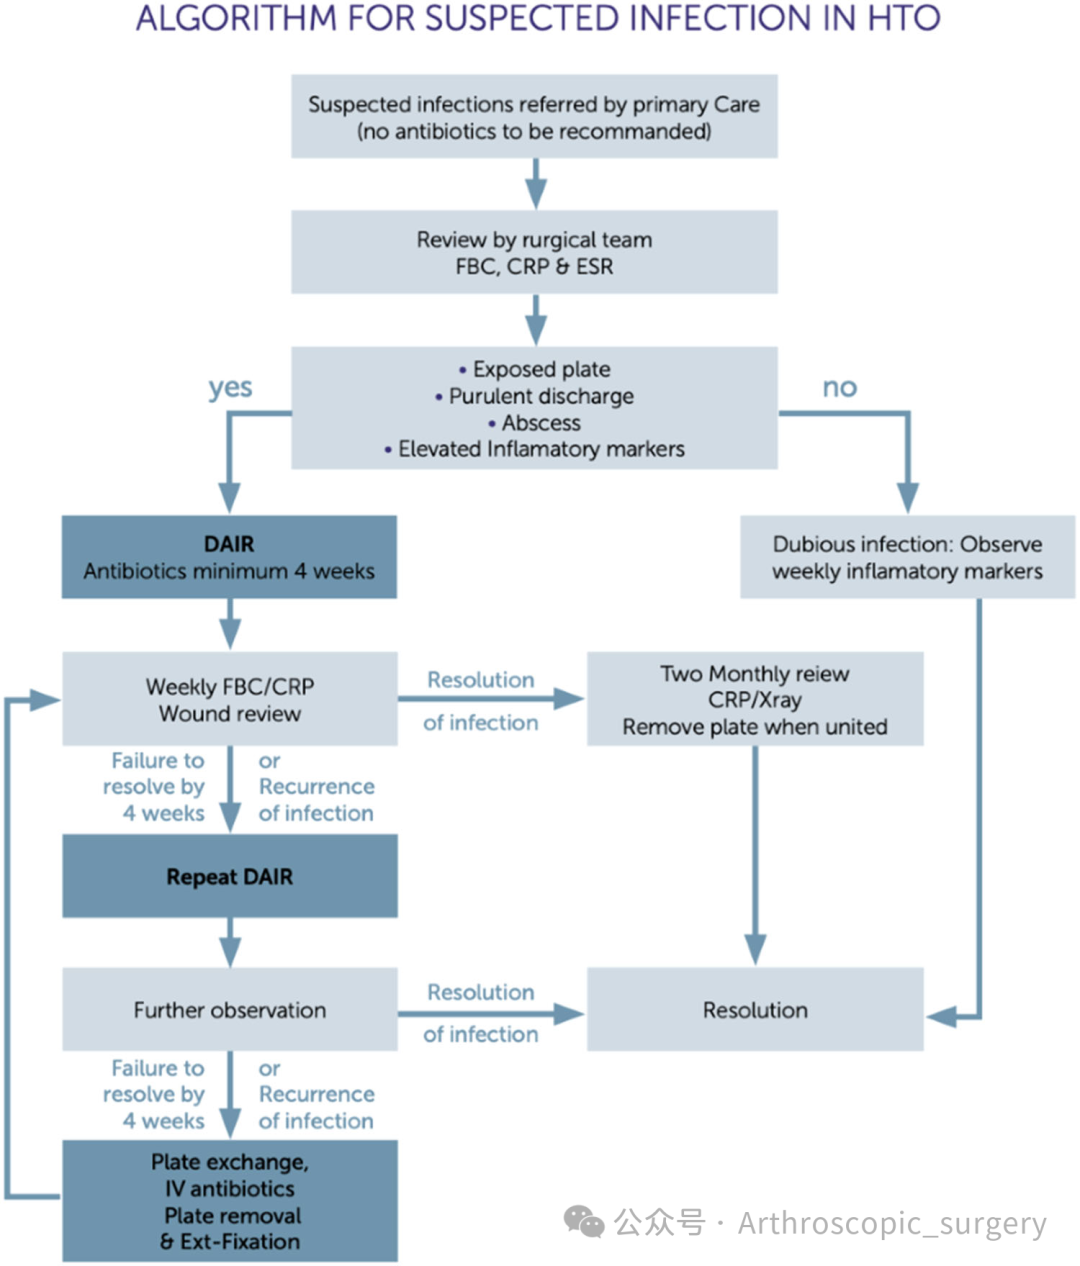

Algorithm summarising the ideal strategy to treat infection following knee osteotomy (high tibial osteotomy [HTO]).